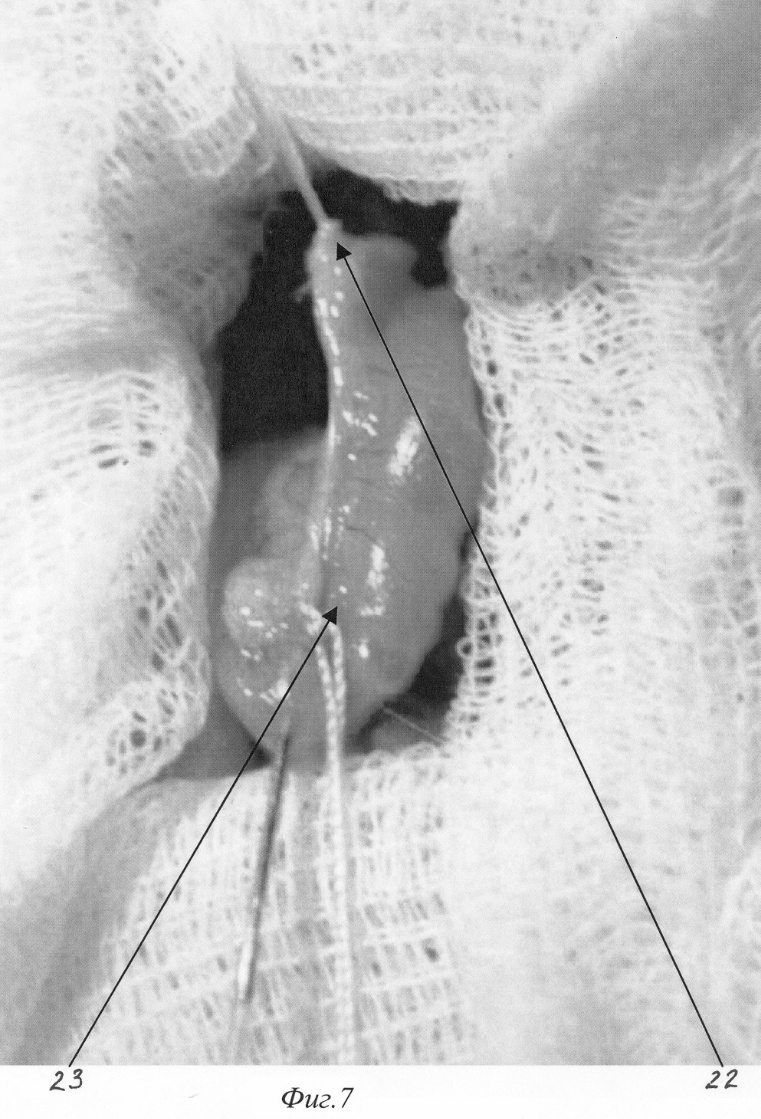

Изобретение относится к медицине, а именно к экспериментальной хирургии, и может быть использовано для моделирования острого деструктивного панкреатита у крыс. Близким решением является способ моделирования, разработанный Aho HJ, Koskensalo SM, и Nevalainen TJ, описанный в статье Experimental pancreatitis in the rat. Sodium taurocholate-induced acute haemorrhagic pancreatitis. Scand J Gastroenterol 15: 411-416, 1980. Который заключается в трансдуоденальной катетеризации общего желчного протока и введение таурохолата натрия (0,4 мл 4% раствора) в общий желчный проток и протоки поджелудочной железы. При использовании данного способа моделирования острого деструктивного панкреатита патогенетические механизмы, лежащие в основе большого количества летальных исходов, отличаются от таковых при развитии острого панкреатита в клинике. Так, таурохолат, являясь гемолитическим ядом, при применении в вышеуказанных концентрациях вызывает внутрисосудистый гемолиз. Другим отрицательным свойством данной модели является невозможность влияния на площадь панкреонекроза. Немаловажным фактором, влияющим на интрапанкреатическую активацию ферментов поджелудочной железы, является уровень рН в ее протоковой системе, что никак не учитывается в данной модели. Задачей изобретения является разработка модели острого панкреатита, наиболее оптимально соответствующей патогенетическим механизмам, имеющим место при развитии острого панкреатита у человека, позволяющей регулировать площадь панкреонекроза, а также снижение летальности, обусловленной гемолитическим действием вводимого в протоки раствора. Поставленная задача решаются тем, что для моделирования острого деструктивного панкреатита вместо раствора таурохолата натрия мы используем трансдуоденальное внутрипротоковое введение специальной буферной системы, содержащей соль желчной кислоты при оптимальной для интрапанкреатической активации ферментов рН. Для возможности управления площадью панкреонекроза мы используем различное наложение (дистальнее или проксимальнее места впадения добавочного протока поджелудочной железы в общий желчный проток) лигатуры, что обеспечивает развитие тотального или субтотального панкреонекроза. Изобретение поясняется фигурами: – на фиг.1 изображено строение протоковой системы крысы (1); – на фиг.2 изображено строение протоковой системы крысы (2); – на фиг.3 изображен первый этап моделирования (срединная лапаротомия); – на фиг.4 изображен второй этап моделирования (выведение органов в рану); – на фиг.5 изображен третий этап моделирования (пункция двенадцатиперстной кишки и катетеризация общего желчного протока); – на фиг.6 изображен пример наложения турникетов для воспроизведения субтотального панкреонекроза; – на фиг.7 изображен пример наложения турникетов для воспроизведения тотального панкреонекроза; – на фиг.8 изображен пятый этап моделирования – ушивание лапаротомной раны. Способ осуществляется следующим образом. Операция проводится с соблюдением правил асептики и антисептики под эфирным наркозом. После обработки операционного поля послойно вскрывается брюшная полость (верхнесрединная лапаротомия) на протяжении 2-3 см (фиг.3). Операционное поле отгораживается стерильными салфетками. При вскрытии брюшной полости в рану выводится петля двенадцатиперстной кишки (фиг.2. 12, фиг 4). В гепатодуоденальной связке определяется общий желчный проток крысы диаметром 0,3-0,5 мм (фиг.2. 11, фиг.4. 16 ). На расстоянии приблизительно 1,5 см от ворот печени (фиг.2. 10) в общий желчный проток по задней поверхности впадает главный панкреатический проток (фиг.2. 9), который собирает секрет от желудочной и селезеночной частей поджелудочной железы и имеет диаметр приблизительно около 0,2-0,3 мм, что лучше видно при рассечении связки аналоги lig. gastrocolicum и отведении желудка кверху (фиг.1). При этом мы увидим дистальную часть общего желчного протока (фиг.1. 2), впадающий в него главный панкреатический проток (фиг.1. 3), желудочную часть поджелудочной железы (фиг.1. 7), прилежащую к задней стенке желудка (фиг.1. 4), и селезеночную часть поджелудочной железы (фиг.1. 6), прилежащую к воротам селезенки (фиг.1. 5). Также при этом доступе можно увидеть и дуоденальную часть поджелудочной железы (фиг.1. 8), дренирующуюся дополнительным протоком (фиг.1. 1), который впадает в общий желчный проток по задней его поверхности на расстоянии около 0,5 см от места вхождения общего желчного протока в стенку двенадцатиперстной кишки. Место впадения дополнительного панкреатического протока в общий желчный проток можно увидеть и при выведении ДПК, как это показано на фиг.2. 19. Интрамуральный отдел общего желчного протока (фиг.2. 14) открывается в просвет ДПК, что можно увидеть через стенку кишки (фиг.2. 14, фиг.4. 17). Найдя место впадения общего желчного протока от него отступают около 0,5 см в этом месте производят пункцию двенадцатиперстной кишки зондом, диаметром 0,3 мм (фиг.5. 19), который через большой дуоденальный сосочек проводится в общий желчный проток до середины расстояния между местами впадения панкреатических протоков (фиг.5. 19). После этого на общий желчный проток накладывается два турникета. Один выше места впадения основного панкреатического протока (фиг.6. 20, фиг.7. 22), второй, в зависимости от того, какую форму панкреатита необходимо воспроизвести (тотальную или субтотальную), выше (фиг.6. 21) или ниже (фиг.7. 23) места впадения добавочного протока поджелудочной железы. Турникеты затягивают. В проток при помощи насоса для микроинфузий вводят 0,3 мл буфера (содержащего 0,3 г трис-гидроксиметил-аминометана и 0,6 г дезоксихолата натрия в 100 мл при рН 8,8) при скорости потока 0,07 мл в минуту. Турникеты с протоков снимают спустя минуту после прекращения введения буфера и удаляют катетер из протока. После создания модели органы погружаются в брюшную полость. Убираются отгораживающие салфетки. Брюшная полость послойно ушивается отдельными шелковыми швами (фиг.8). Рана обрабатывается раствором антисептика. Пример конкретного применения. Исследование проведено на 100 самках крыс линии Вистар массой 200 г. С целью подтверждения наличия острого деструктивного панкреатита производилось морфологическое исследование образцов поджелудочной железы на сроке 12 часов (как наиболее информативного срока). Образцы поджелудочной железы забирались, фиксировались в 10% растворе нормального формалина, обезвоживались, заливались в парафин, готовились парафиновые срезы, которые затем окрашивались гематоксилин-эозином. Также производилось исследование активности амилазы в сыворотке крови и перитонеальном экссудате амилокластическим методом со стойким крахмальным субстратом по Каравею. Кроме этого оценивалась летальность за первые сутки с момента моделирования. Полученные данные сравнивали с данным контрольной группы (интактные животные). Так, нормальные значения активности амилазы, вычисленные для нашей лаборатории, – 61,76 г/ч/л. После моделирования острого панкреатита описанным выше методом через 12 часов с момента моделирования активность амилазы сыворотки крови при тотальном панкреонекрозе достигает уровня 144,77±3,2 г/ч/л (р<0,01), а перитонеального экссудата 1237,36±7,4 г/ч/л (р<0,01) г/ч/л, при субтотальном панкреонекрозе 160,56±4,3 г/ч/л (р<0,01) и 1548,21±8,3 г/ч/л (р<0,01) – соответственно. При морфологическом исследовании получены следующие результаты: Макроскопическая картина при вскрытии брюшной полости и грудной клетки крысы после моделирования тотального панкреонекроза. При вскрытии в брюшной полости до 5 мл серозно-геморрагического выпота во всех отделах, гиперемия париетальной и висцеральной брюшины брыжейка тонкой кишки отечна, с множественными мелкими очагами стеатонекроза. Печень не увеличена, темно-вишневого цвета, поверхность ее гладкая, края долей заострены. Почки без видимой макроскопической патологии. Селезенка умеренно увеличена в размерах, темно-вишневого цвета. При вскрытии просвета желудка и ДПК определяются множественные мелкие (точечные) эрозии шоколадного цвета. Поджелудочная железа резко отечна с участками стеатонекроза размерами от 0,3 до 0,5 см в диаметре. В области желудочно-дуоденальной части имеются участки геморрагического панкреонекроза размерами до 0,3 см в диаметре. Отмечается отек забрюшинной клетчатки. При вскрытии грудной клетки определяется гиперемия плевры и небольшое количества светлого выпота. Поверхность легких гладкая, буроватого цвета с множественными точечными кровоизлияниями. Сердце без видимых макроскопических изменений. Морфологическое исследование поджелудочной железы (окраска гематоксилин-эозином увеличение 20 В дуоденальной части определяется зона тотального некроза с участками геморрагии, массивной нейтрофильно-макрофагальной инфильтрацией. Структура ацинусов не сохранена. В желудочной части имеет место крупноочаговый панкреонекроз с единичными участками геморрагии, клеточными структурами разрушенных панкреатоцитов, нейтрофильно-макрофагальной инфильтрацией. В зонах, удаленных от очагов некроза, структура ацинусов сохранена. В участках, примыкающих к зонам некроза, панкреатоциты имеют вакуолизированную цитоплазму, ядра неправильной формы. В селезеночной части определяются множественные центролобулярные некрозы. Имеется значительное количество ацинусов с сохраненной структурой, встречаются интактные островки Лангерганса. Макроскопическая картина при вскрытии брюшной полости и грудной клетки крысы после моделирования субтотального панкреонекроза. При вскрытии брюшной полости определяется до 3-4 мл серозно-геморрагического выпота. Париетальная и висцеральная брюшина гиперемирована во всех отделах. Брыжейка тонкой кишки отечна, с умеренным количеством мелких очагов стеатонекроза. Печень не увеличена, темно-вишневого цвета, поверхность ее гладкая, края долей заострены. На разрезе структура паренхемы не изменена, сосуды полнокровны. Селезенка умеренно увеличена в размерах, темно-вишневого цвета. Почки увеличены серовато-бурого цвета, на разрезе отчетливо просматривается кортикальный слой, темно-вишневого цвета с серым оттенком. При вскрытии просвета желудка и ДПК определяются множественные мелкие эрозии шоколадного цвета. Поджелудочная железа резко отечна с участками стеато и геморрагического панкреонекроза в желудочной части до 0,3 см в диаметре и участками стеатонекроза в парапанкреатической клетчатке. Дуоденальная часть железы отечна. При вскрытии грудной клетки определяется гиперемия плевры и небольшое количества светлого выпота. Поверхность легких гладкая, буроватого цвета с множественными точечными кровоизлияниями. Сердце без видимых макроскопических изменений. Морфологическое исследование поджелудочной железы (окраска гематоксилин-эозином увеличение 20 В дуоденальной части определяется интерстициальный отек с геморрагическим пропитыванием. Структура ацинусов сохранена. В желудочной части имеет место крупноочаговый панкреонекроз с единичными участками геморрагий, клеточными структурами разрушенных панкреатоцитов, нейтрофильно-макрофагальной инфильтрацией. В зонах, удаленных от очагов некроза, структура ацинусов сохранена. В участках, примыкающих к зонам некроза, панкреатоциты имеют вакуолизированную цитоплазму, ядра неправильной формы. В селезеночной части определяются множественные центролобулярные некрозы. Имеется значительное количество ацинусов с сохраненной структурой, встречаются интактные островки Лангерганса. При моделировании острого панкреатита летальность к первым суткам составила 80,6% при тотальном панкреонекрозе и 56,3% при субтотальном панкреонекрозе. В образцах крови, взятых при тотальном и при субтотальном панкреонекрозе, гемолиза не выявлено. Таким образом, поставленная задача достигнута, во первых, за счет уменьшения количества желчной кислоты в водимом в протоки растворе, во вторых, за счет поддержания рН вводимого раствора на оптимальном для активации ферментов уровне, в третьих, за счет наложения турникета до или после места впадения дополнительного протока поджелудочной железы в общий желчный проток и управления площадью некроза. В результате применения данного способа моделирования острого панкреатита развивается крупноочаговый некроз поджелудочной железы (тотальный или субтотальный), что, в свою очередь, приводит к: 1. Выявлению достоверных признаков развития острого панкреатита (морфологических и биохимических). 2. Возможности управления площадью некроза. 3. Снижению уровня летальности, связанной с гемолитическим действием солей желчных кислот. Формула изобретения